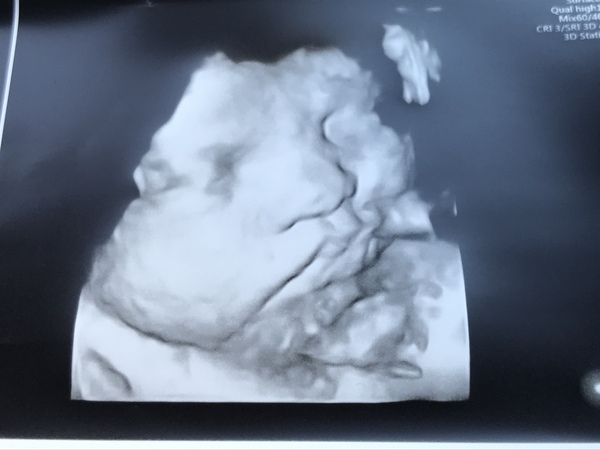

Final growth scan done at 37+1, still on track as before. Currently estimated at 6lb 6 and on track for about 8lb. All measurements normal so no more appointments or scans apart from MW until induction at 40wks.

She still looks the same on the photo too, same position, head down and looking to my right 😍